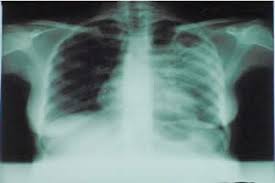

Dias 24 e 25 /03- Palestras com as Equipes de Saúde da Família (Escolas e sala de espera) nas 8 unidades do Município; além da solicitação dos exames de RX de tórax e Baciloscopia para comprovar diagnóstico (durante e depois da campanha);